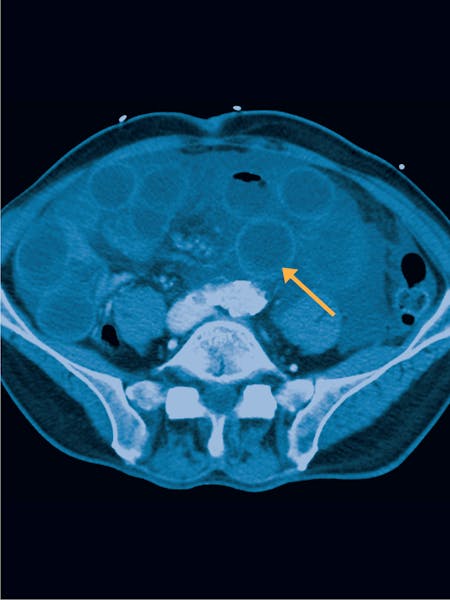

- Angio CT și Angio RMN: Aceste investigații imagistice, care folosesc substanțe de contrast, sunt cele mai eficiente metode pentru vizualizarea arborelui vascular mezenteric și a fluxului sangvin către intestin.

- CT abdominal și RMN abdominal: Aceste metode sunt utilizate în cazurile în care diagnosticul este incert sau pentru a exclude alte afecțiuni. Ele pot oferi imagini detaliate ale structurii organelor abdominale. .